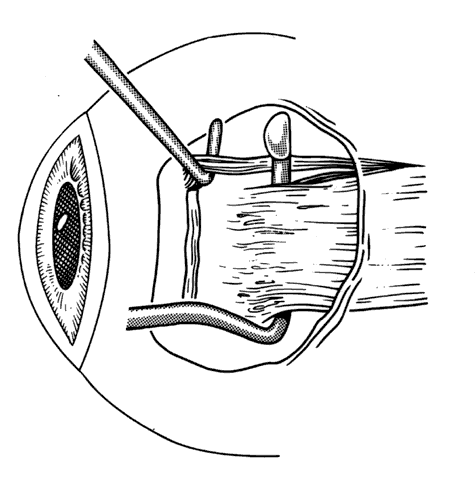

The anesthetic level should provide the patient sufficient comfort. The new rapid-acting intravenous sedation agents provide the surgeon with sufficient sedation to perform some procedures with topical or perimuscular anesthesia. This provides an opportunity for patient cooperation for intraoperative suture adjustment. Once the anesthetic has been administered, the surgeon can proceed with forced duction testing (Fig. 11). If the patient is under general anesthesia or a retrobulbar block has been used, the globe can be moved back and forth and then released to seek its natural position of rest. The “spring back balance test,” popularized by Jampolsky, Scott and Rosenbaum, provides the surgeon with information on the extent and location of restriction (Fig. 12). Forced ductions should include torsional forced ductions to determine if the oblique muscles are restricted.35 During forced ductions, the surgeon should observe the conjunctiva for underlying restrictive tissue bands. Adhesions between these bands and the conjunctiva will cause the conjunctiva to pucker.

Fig. 11. Forced ductions are used to determine the presence and extent of restrictive forces on the globe. This photograph illustrates difficulty abducting the globe due to an inelastic medial rectus muscle resulting from previous resection of the medial rectus muscle.

Fig. 12. The spring back balance test may be performed at any time during surgery. A. The globe is moved from right to left several times and is then released. B. Restrictive bands, scar tissue, or contraction of an inelastic muscle will cause the globe to return to the position induced by the restriction.